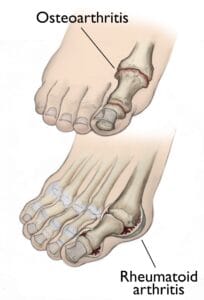

(Top) Osteoarthritis that has progressed to bone rubbing on bone and bone spurs. (Bottom) Swollen, inflamed synovium and joint deformity are signs of rheumatoid arthritis.

Osteoarthritis

Osteoarthritis, also known as degenerative or wear-and-tear arthritis, is a common problem for many people after they reach middle age, but it may occur in younger people, too. In osteoarthritis, the cartilage in the joint gradually wears away. As the cartilage wears away, it becomes frayed and rough, and the protective space between the bones decreases. This can result in bone rubbing on bone, and produce painful osteophytes (bone spurs). In addition to age, other risk factors for osteoarthritis include obesity and family history of the disease. Osteoarthritis develops slowly, causing pain and stiffness that worsen over time.Rheumatoid Arthritis

Rheumatoid arthritis is a chronic disease that can affect multiple joints throughout the body, and often starts in the foot and ankle. It is symmetrical, meaning that it usually affects the same joint on both sides of the body. Rheumatoid arthritis is an autoimmune disease. This means that the immune system attacks its own tissues. In rheumatoid arthritis, immune cells attack the synovium covering the joint, causing it to swell. Over time, the synovium invades and damages the bone and cartilage, as well as ligaments and tendons, and may cause serious joint deformity and disability. The exact cause of rheumatoid arthritis is not known. Although it is not an inherited disease, researchers believe that some people have genes that make them more susceptible. There is usually a trigger, such as an infection or environmental factor, which activates the genes. When the body is exposed to this trigger, the immune system begins to produce substances that attack the joints.